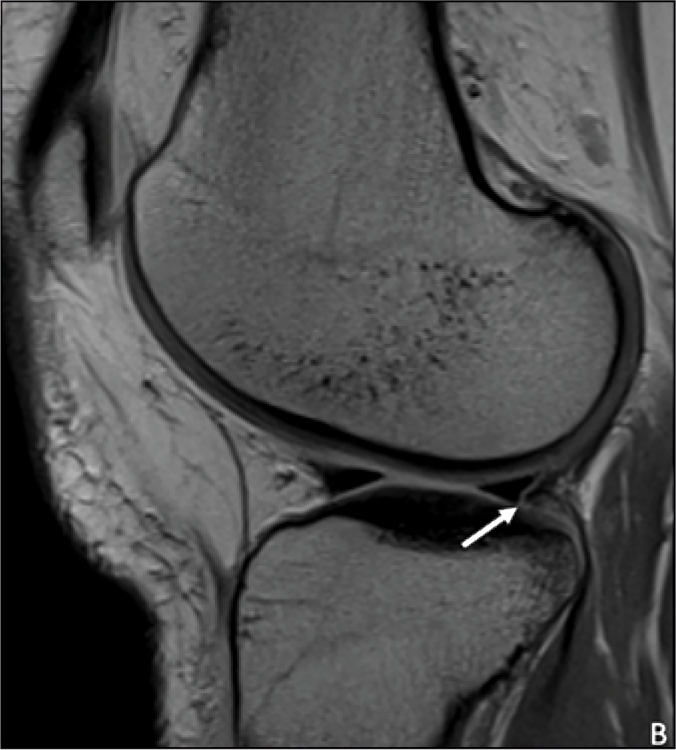

Check out our new @AJR_Radiology paper on lateral meniscal oblique radial tears (LMORT lesions), an important posterior lateral meniscal tear pattern in patients with acute ACL injury. @MichaelAlaiaMD @NYUImaging @nyulangoneortho @nyulangone

This study assesses MRI's utility in distinguishing lateral meniscal oblique radial tears from other meniscal tears in patients with ACL injury. https://t.co/lDTz7rXZ7Y